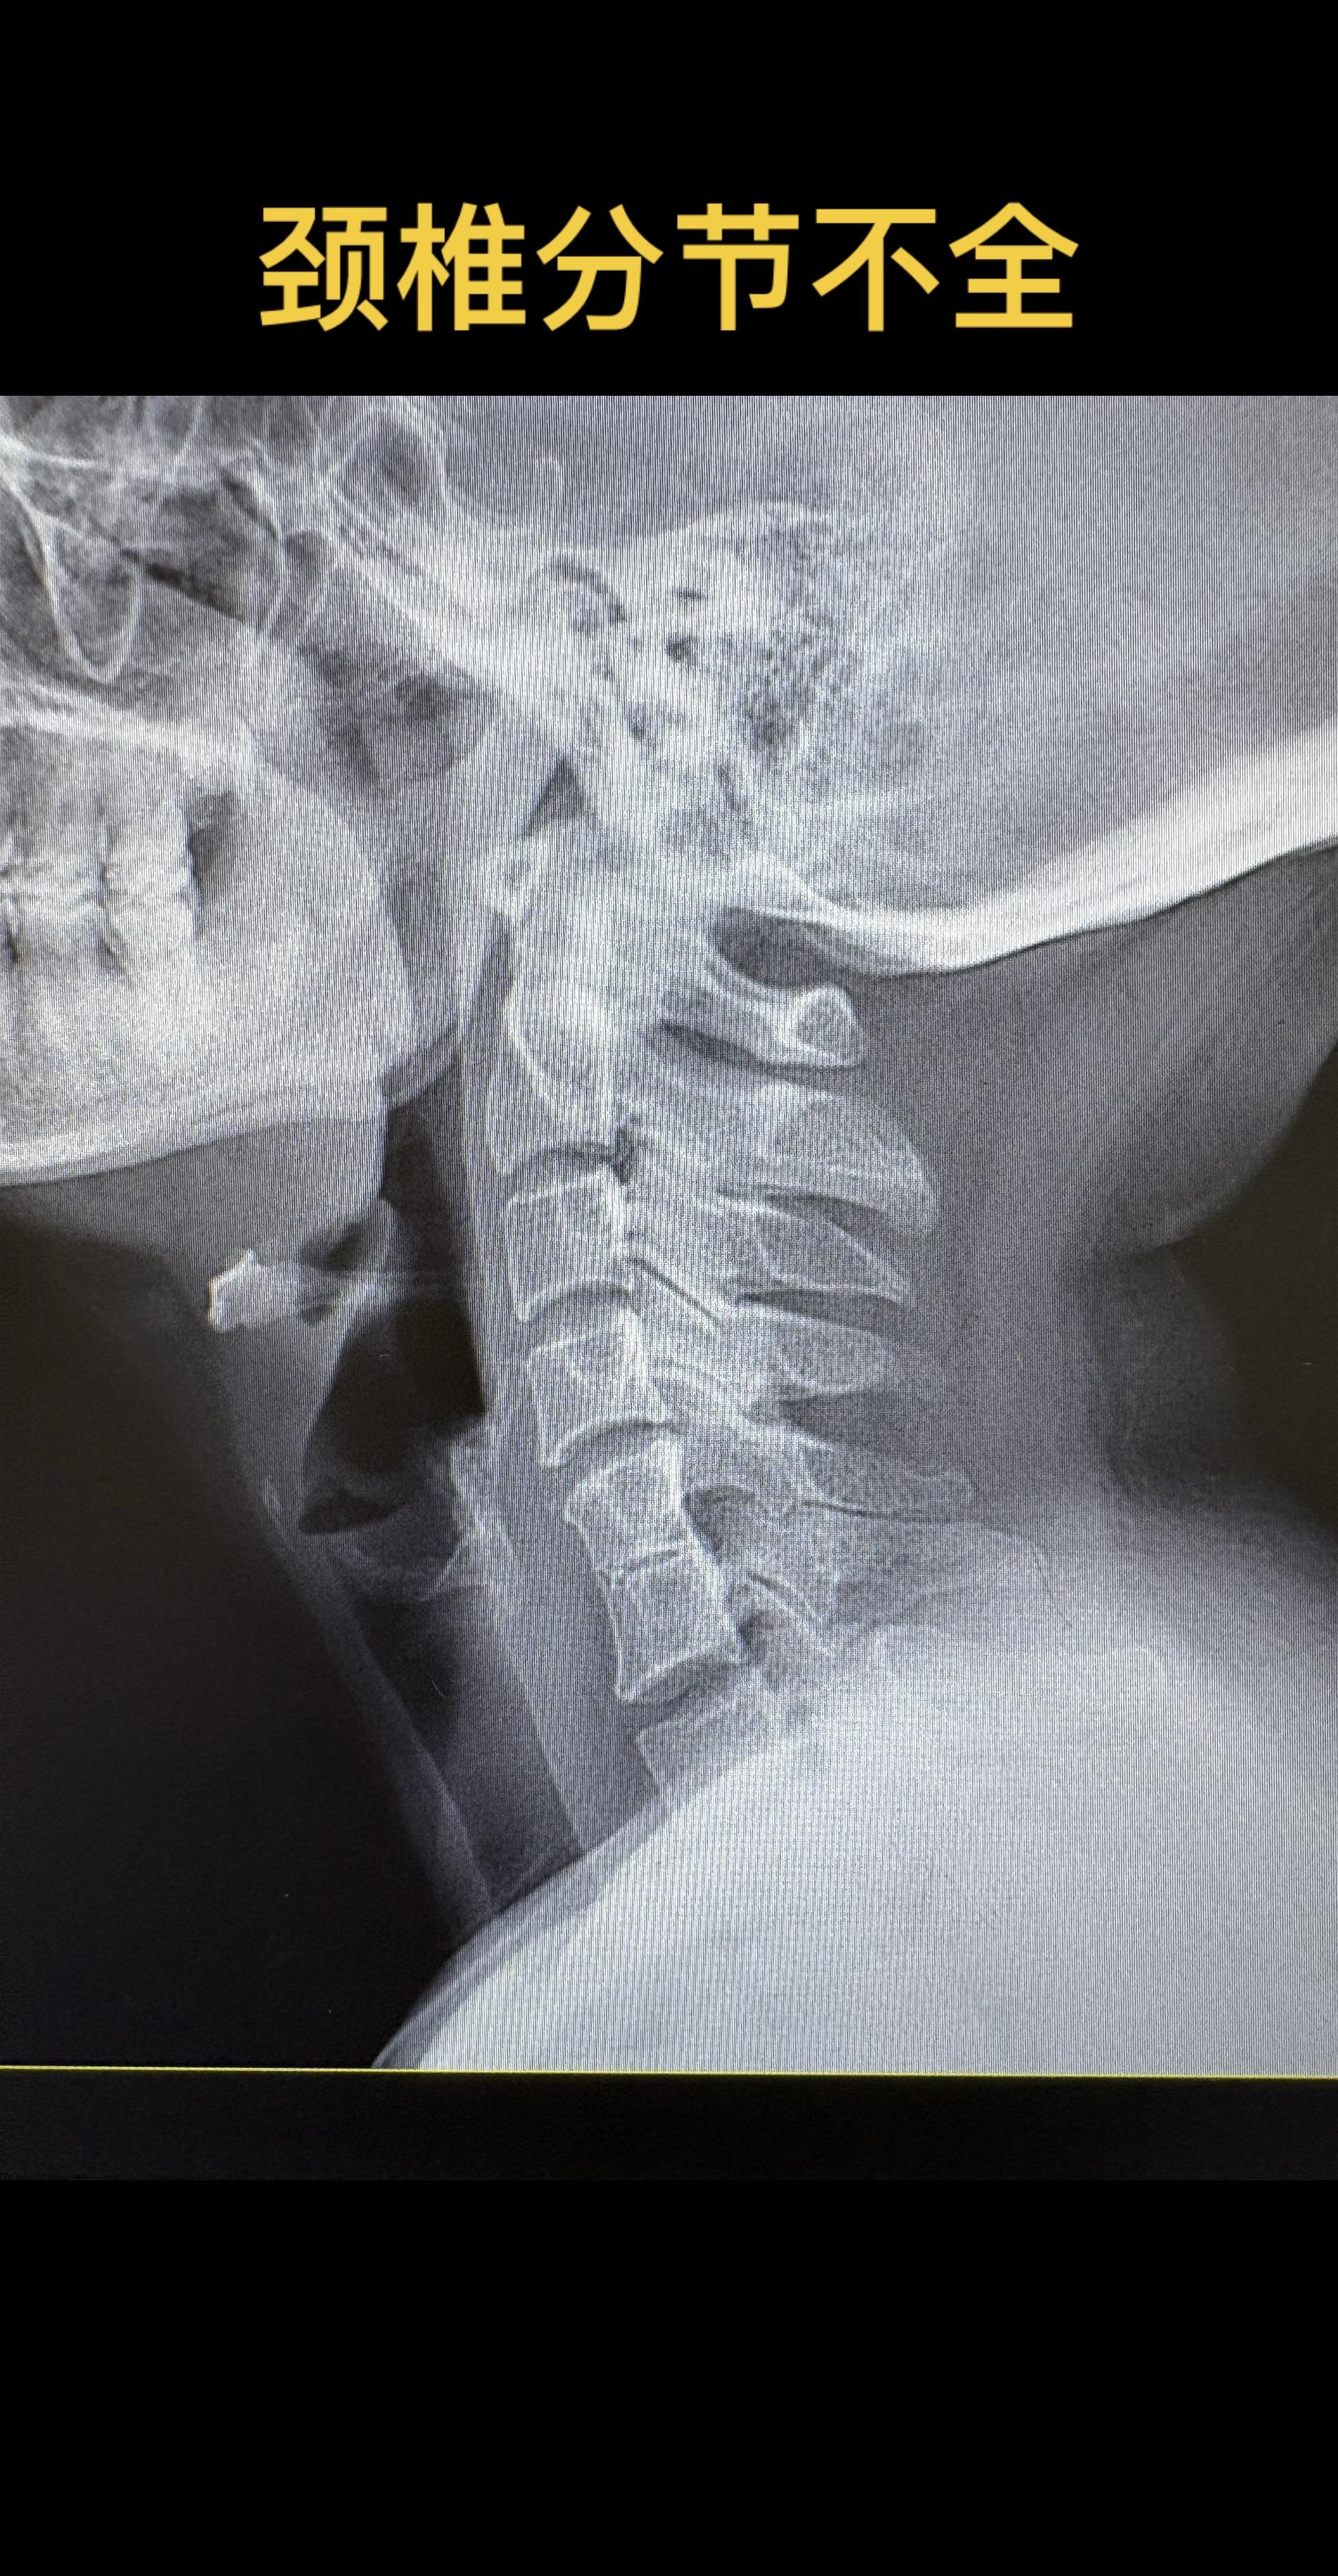

颈56椎体分节不全。一种常见的颈椎发育畸形  klippel-feil综合征